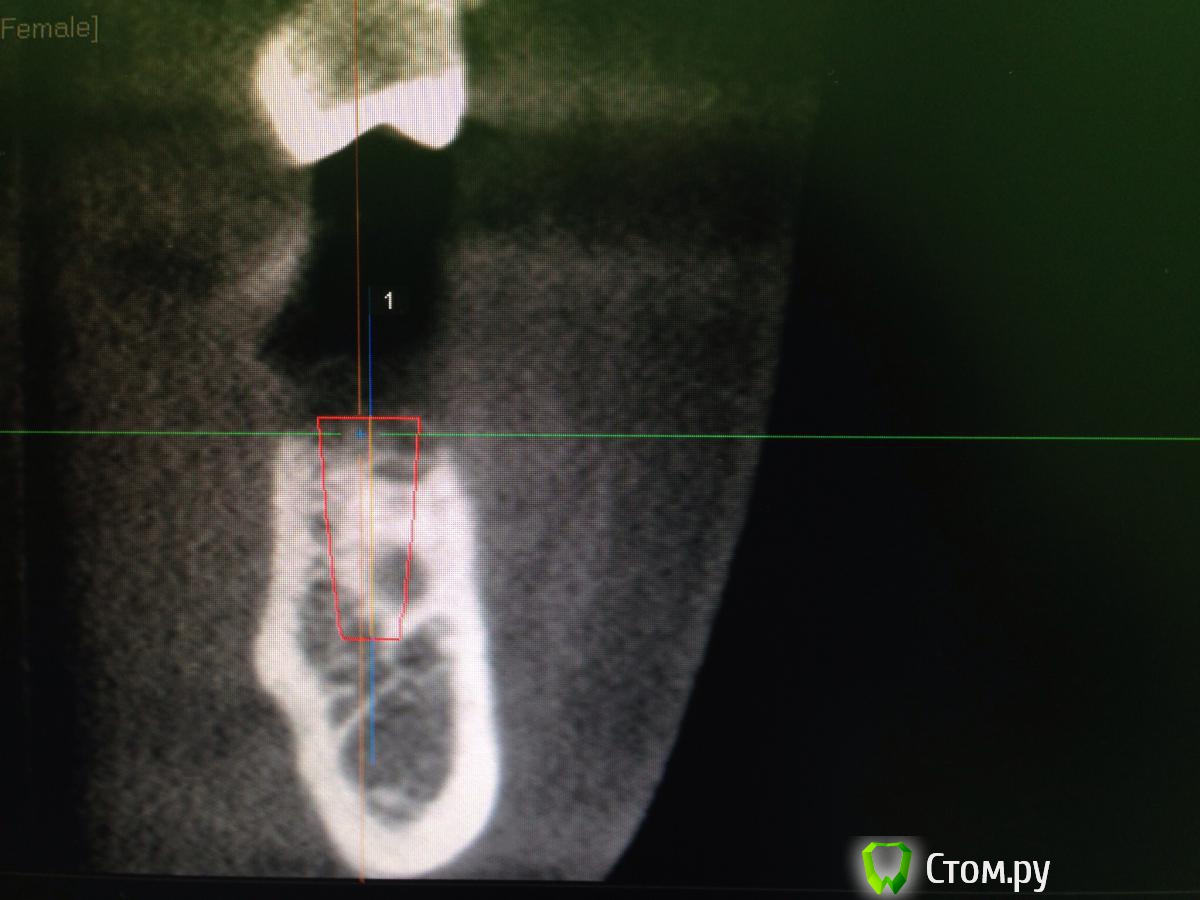

diesel87 Опубликовано 10 февраля, 2014 Поделиться Опубликовано 10 февраля, 2014 Планируется установка винта в области удаленного 3 месяца назад 36 зуба, размером 4,8*12; вот срезы кт, винт планирую в такой позиции, волнует костная пластика, нужна ли она и где именно и не слишком ли глубоко будет стоять винт по отношению к соседним зубам? Ссылка на комментарий

Acidrocker Опубликовано 10 февраля, 2014 Поделиться Опубликовано 10 февраля, 2014 имхо, на миллиметр еще можно заглубить.. по ширине, может, лучше что-нибудь около 4,0-4,3? Ссылка на комментарий

diesel87 Опубликовано 10 февраля, 2014 Автор Поделиться Опубликовано 10 февраля, 2014 На мм углубить думаю судя уже по высоте на операции, но не будет ли слишком глубоко? Можно ли сделать так чтоб оставить немного по высоте не в кости и засыпать графтом и мембраной укрыть? А по поводу диаметра, 4,3 советуете исходя из толщины межкорневой перегородки? Ссылка на комментарий

Maxfac Опубликовано 10 февраля, 2014 Поделиться Опубликовано 10 февраля, 2014 (изменено) На мм углубить думаю судя уже по высоте на операции, но не будет ли слишком глубоко? Можно ли сделать так чтоб оставить немного по высоте не в кости и засыпать графтом и мембраной укрыть? А по поводу диаметра, 4,3 советуете исходя из толщины межкорневой перегородки?А что за систему хотите ставить? По мне, вариант с графтом и мембраной - от лукавого. Ставьте вровень, это не то "глубоко", из-за которого стоило бы париться) Изменено 10 февраля, 2014 пользователем Maxfac 1 Ссылка на комментарий

Acidrocker Опубликовано 10 февраля, 2014 Поделиться Опубликовано 10 февраля, 2014 На мм углубить думаю судя уже по высоте на операции, но не будет ли слишком глубоко? Можно ли сделать так чтоб оставить немного по высоте не в кости и засыпать графтом и мембраной укрыть? А по поводу диаметра, 4,3 советуете исходя из толщины межкорневой перегородки?4.5 или даже 4.0, исходя из количества кости вокруг шейки. на имплантиуме пришеечная резорбция бывает достаточно выражена. не надо графт и мембрану, если можно заглубить на мм) 1 Ссылка на комментарий

diesel87 Опубликовано 10 февраля, 2014 Автор Поделиться Опубликовано 10 февраля, 2014 4.5 или даже 4.0, исходя из количества кости вокруг шейки. на имплантиуме пришеечная резорбция бывает достаточно выражена. не надо графт и мембрану, если можно заглубить на мм)4.5 или даже 4.0, исходя из количества кости вокруг шейки. на имплантиуме пришеечная резорбция бывает достаточно выражена. не надо графт и мембрану, если можно заглубить на мм)Толщина кости 8 мм, а графт и мембрану я больше вестибулярно хотел положить, там провальчик не большой есть, а что по поводу резорбции вокруг Implantium? Ссылка на комментарий

Sahan Опубликовано 10 февраля, 2014 Поделиться Опубликовано 10 февраля, 2014 Платформу на 1 мм заглубить, соотношение будет самое оно . Имплантат лучше 4,2на 10мм, хотя 4,8 тоже сойдет 1 Ссылка на комментарий

Sahan Опубликовано 10 февраля, 2014 Поделиться Опубликовано 10 февраля, 2014 Учитывая что Вам нужно на 1 мм утопить имплантат, а на крайнем фото до канала осталось около 2 мм, 12 мм будет впритык к каналу. Что , как писал коллега выше, может боком вылезти. Ссылка на комментарий